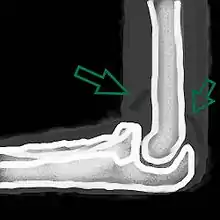

رسم يظهر علامة الشراع والتي تدل على انصباب.